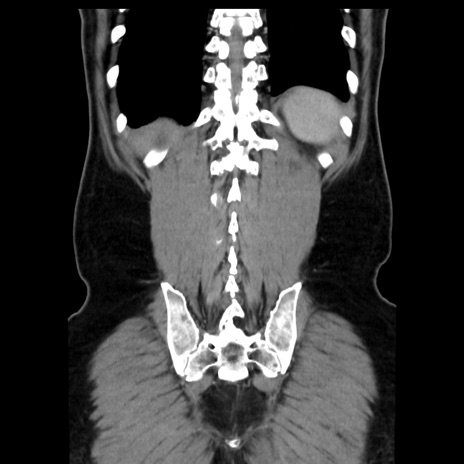

症例16(冠状断像)

【症例】 70歳代男性

【主訴】 腹痛、嘔吐

【現病歴】 約1ヶ月前より間欠的に腹痛と嘔吐あり、当院消化器内科を受診したところCTで多発する肝臓のLDAを指摘され、精査中であった。以降は消化器症状は安定していたが、2日前より嘔気と腹痛があり、同日より排便・排ガスが消失した。改善認めず、 本日、救急外来を受診した。

【既往歴】 大腸ポリープ切除後。

【身体所見】意識清明・会話良好、BT 36.3℃、BP 127/80mmHg、 P 80bpm、腹部:膨満あり、平坦・軟、上腹部正中および下腹部正中に圧痛あり、反跳痛なし、筋性防御なし。

【データ】WBC 7200、CRP 0.77